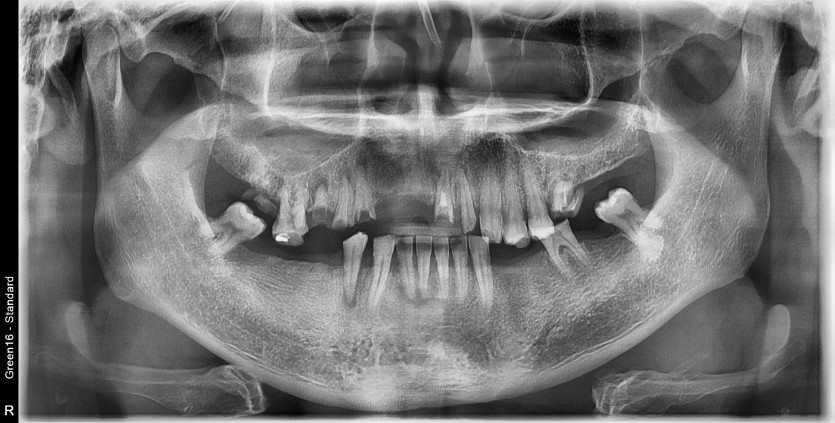

전체 임플란트 증례입니다.

18개의 임플란트로 완성하였습니다.